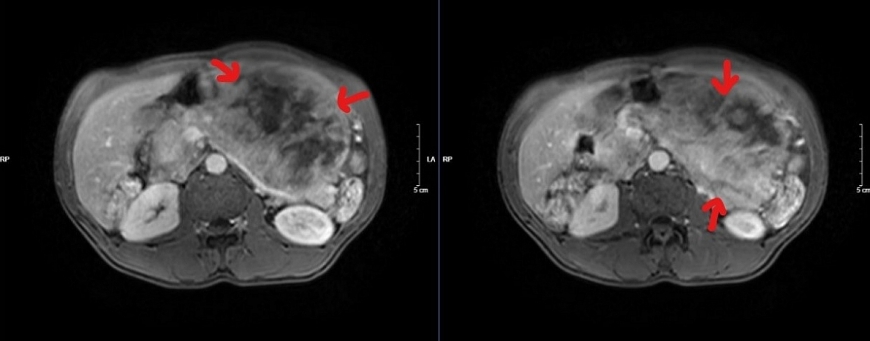

Trường hợp thứ 2: Bệnh nhân N.Q.T, 62 tuổi, có tiền sử viêm dạ dày hơn 10 năm điều trị không thường xuyên. Khoảng 4 năm nay, ông T thấy đau tức thượng vị âm ỉ, nghĩ mình vẫn bị viêm dạ dày nên ông tự ra hiệu thuốc để mua thuốc về uống. Sau khi sử dụng thuốc, triệu chứng có chút thuyên giảm, nhưng không khỏi. Sau đó một năm, thấy bụng to lên nhưng nghĩ rằng béo bụng do tích mỡ, ông T ăn ít hơn để giảm béo, cân nặng không tăng nhưng bụng vẫn to dần. Cho đến 3 tháng gần đây, ăn vào có cảm giác đầy bụng, khó chịu, sờ bụng có khối cứng kể cả lúc đói nên ông T đã quyết định đi khám tại một bệnh viện tư ở thành phố Sơn La. Ở đó, ông được chẩn đoán u ruột non và được chuyển đến Bệnh viện đa khoa tỉnh Sơn La để điều trị tiếp. Tại đây, bệnh nhân được đánh giá là trường hợp bệnh phức tạp nên đã được chuyển lên Bệnh viện Bạch Mai.

Tại Bệnh viện Bạch Mai, ông đã được chẩn đoán mắc bệnh GIST dạ dày và được chỉ định phẫu thuật tại Khoa Phẫu thuật Tiêu hóa - Gan mật tụy. Ca mổ được dự kiến là khó khăn, phức tạp thậm chí có thể không làm được gì. Tuy nhiên, dưới sự quyết tâm, nỗ lực của các phẫu thuật viên dày dặn kinh nghiệm và sự phối hợp của các bác sĩ gây mê hồi sức, sau 3 tiếng tập trung cao độ, kíp phẫu thuật đã cắt được khối u khổng lồ đường kính hơn 30 cm, nặng 5 kg cùng gần như toàn bộ dạ dày của ông T mà không làm tổn thương đến các tạng xung quanh.